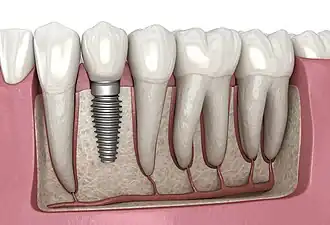

Dental implant, 3D illustration

A dental implant (also known as an endosseous implant or fixture) is a prosthesis that interfaces with the bone of the jaw or skull to support a dental prosthesis such as a crown, bridge, denture, or facial prosthesis or to act as an orthodontic anchor. The basis for modern dental implants is a biological process called osseointegration, in which materials such as titanium or zirconia form an intimate bond to the bone.[1] The implant fixture is first placed so that it is likely to osseointegrate, then a dental prosthetic is added. A variable amount of healing time is required for osseointegration before either the dental prosthetic (a tooth, bridge, or denture) is attached to the implant or an abutment is placed which will hold a dental prosthetic or crown.